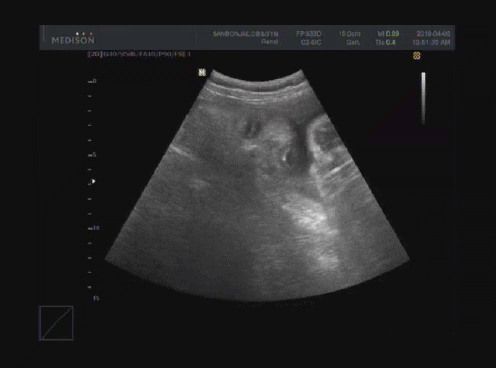

짠짠이 29주 ~ 36주 차

29 ~ 36주.

아내는 날이 갈수록 점점 배가 불러갔고 짠짠이는 엄마 뱃속이 좁다고 매일 난리다. 초음파 사진 모습도 대강 비슷해서 항상 "좁다!!!"라고 하는 것 같다. 엄마 배를 뻥뻥 차서 아내는 잠도 깨고 어떨 때는 아프기까지 했다고. 아내는 이제 정말로 몸이 무겁다는 말을 실감했다. 짠짠이는 자리를 잡아 걱정이 없는데 아내는 뭘 해도 피곤하고 몸이 붓고 뼈마디가 쑤시기 시작했다. 그래도 짠짠이가 나오기 전에 둘만의 시간을 만끽하러 무거운 몸을 이끌고 열심히 다녔다. 여러 가지 모습으로 짠짠이를 맞이할 준비를 하던 시기.

20190406111327V128315-51251627_1.gif 짠짠이 눈, 코, 입. 뭐가 뭔지 모르겠다고요? 저희도 짠짠이 엄마 말고는 아무도 못 알아봤습니다.